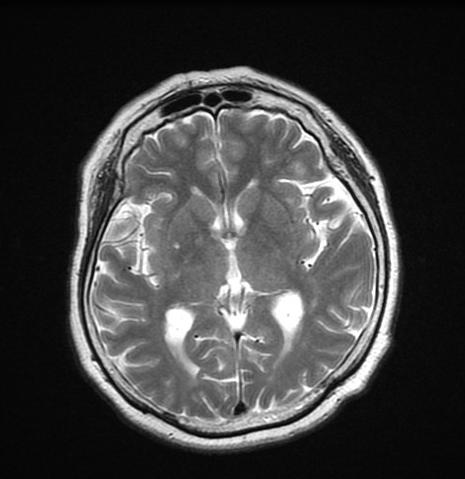

脳ドックでは、MRI検査を中心として自覚症状のない『無症候性脳梗塞』やクモ膜下出血の原因となる未破裂の動脈瘤など、発症前の脳の病気を探し出します。

また、物忘れ脳ドックでは、MRIの画像を利用し、早期アルツハイマー型認知症の診断を行うことができます。